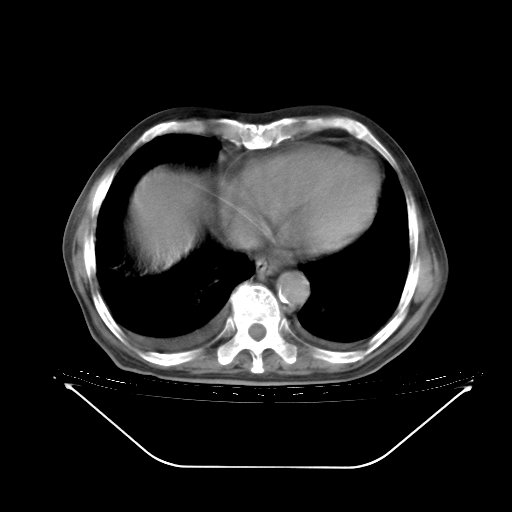

今天复查肺部CT,发现双肺广泛磨玻璃样改变。所以我把3月19日和5月9日相隔50天的肺部CT上传。请大家会诊。

2009年3月19日肺部CT片。

5月9日肺部CT(在4月27日齐鲁医院肺部CT描述部分肺组织磨玻璃样改变,12天后肺组织广泛磨玻璃样改变)